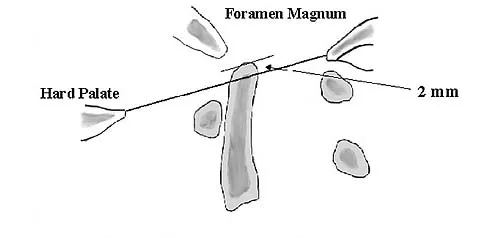

What type of injury is considered the major mechanism of cervical fracture, dislocation, and quadriplegia in contact sports and diving?

Explanation